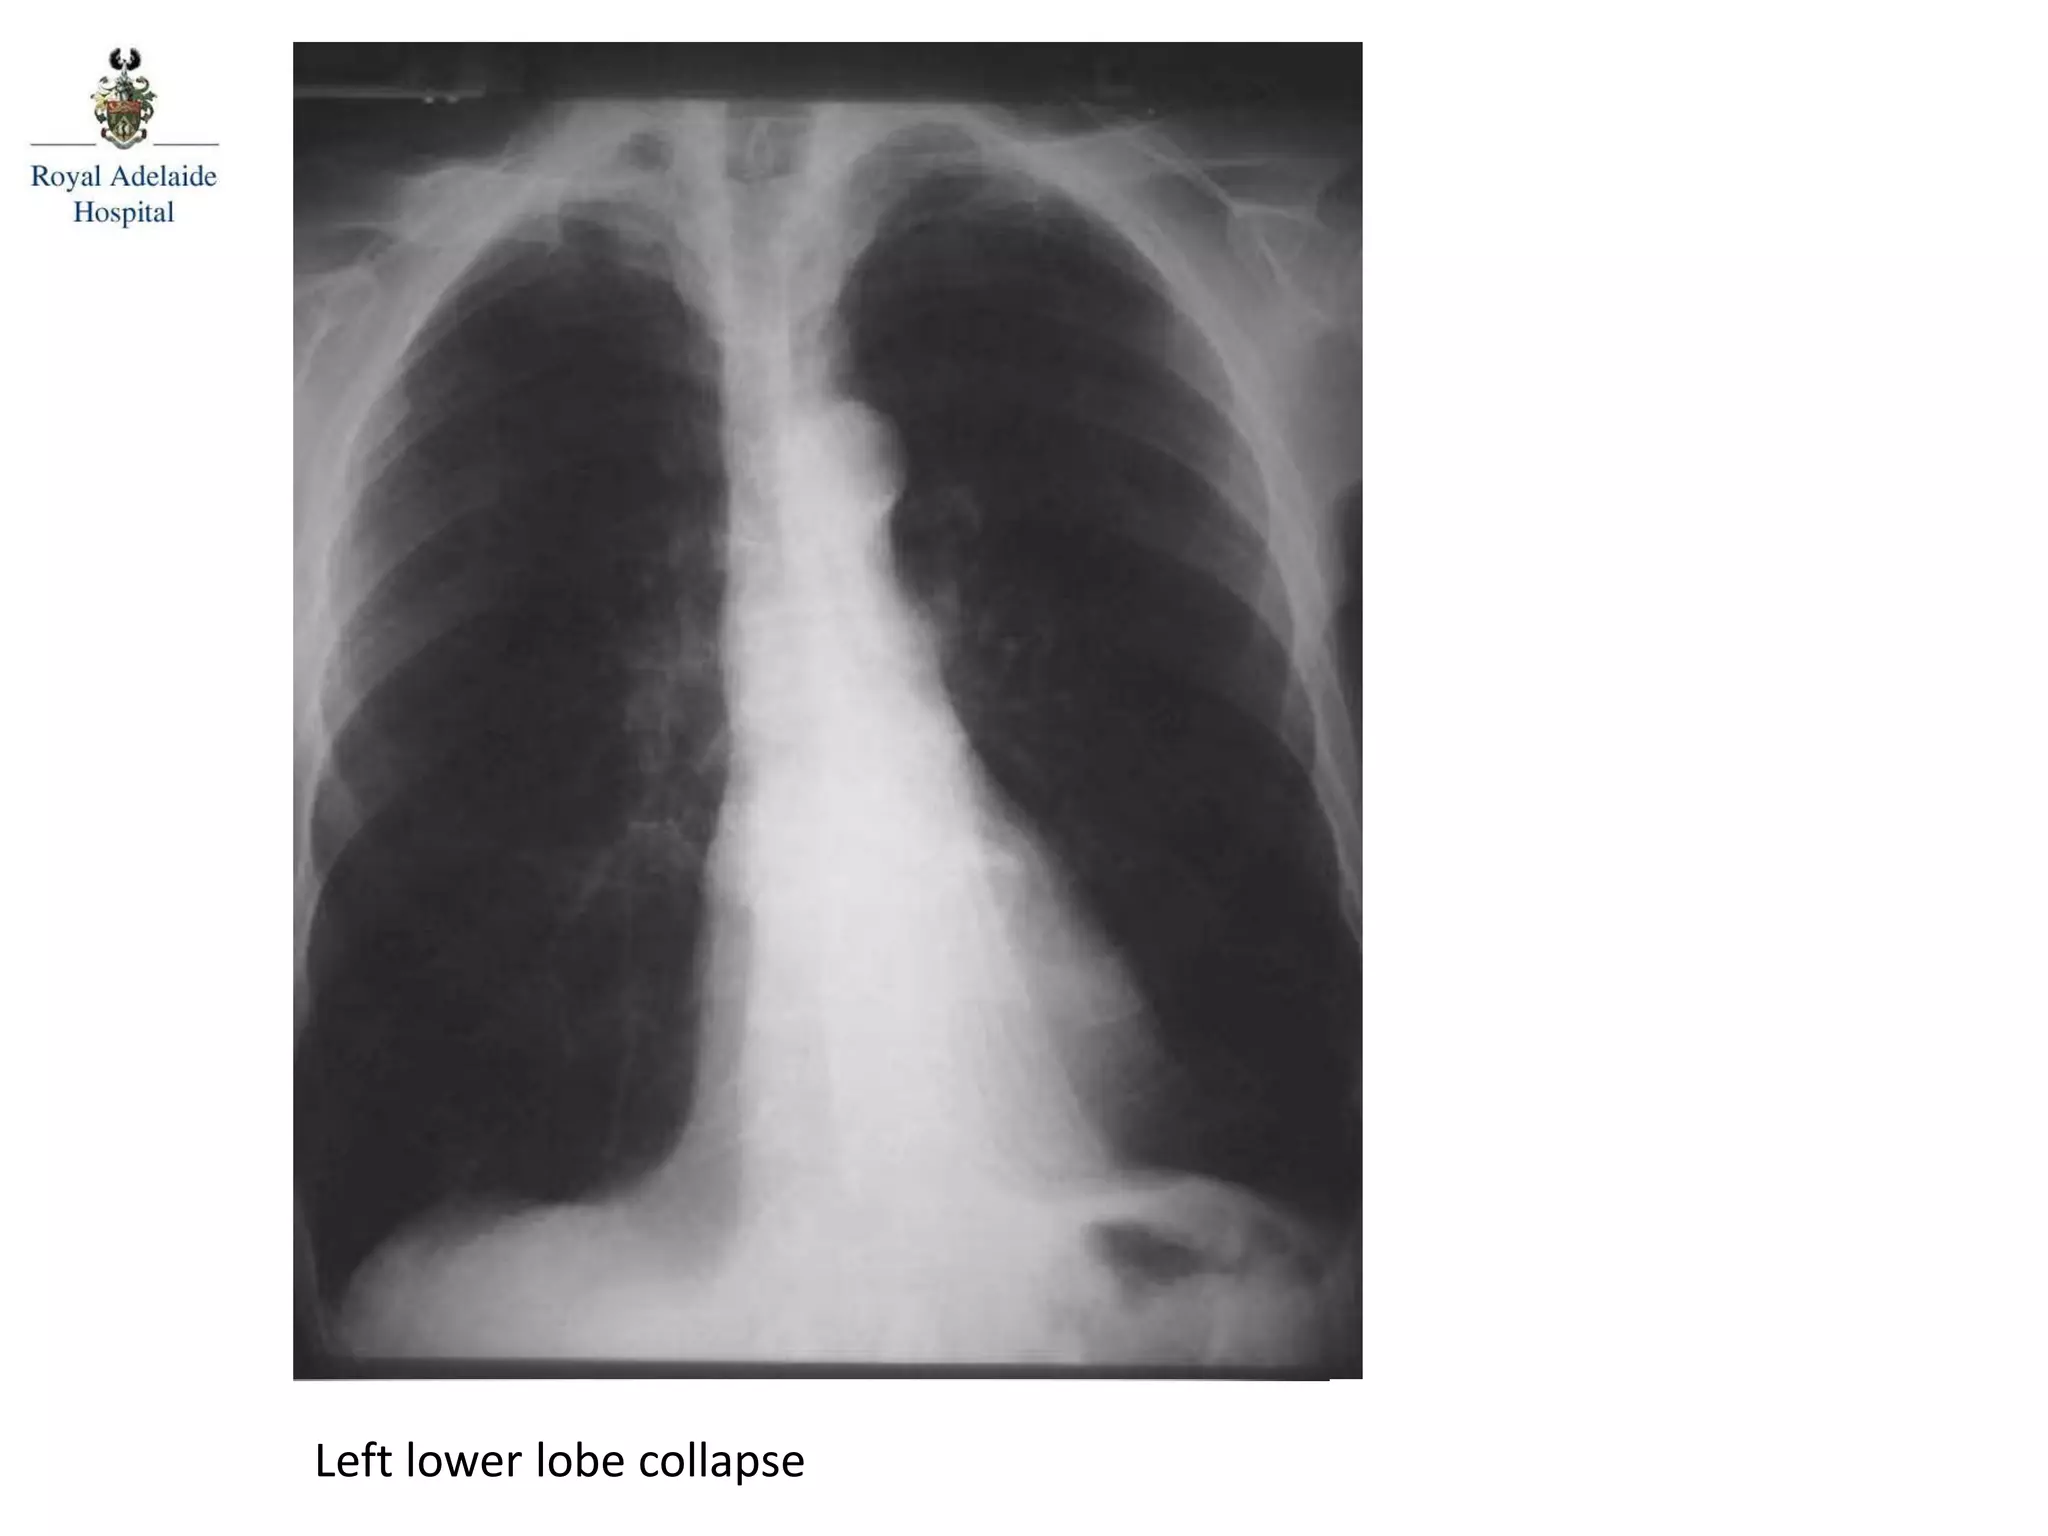

Diagnosis: Left lower lobe collapse (sail sign)

Left lower lobe collapse